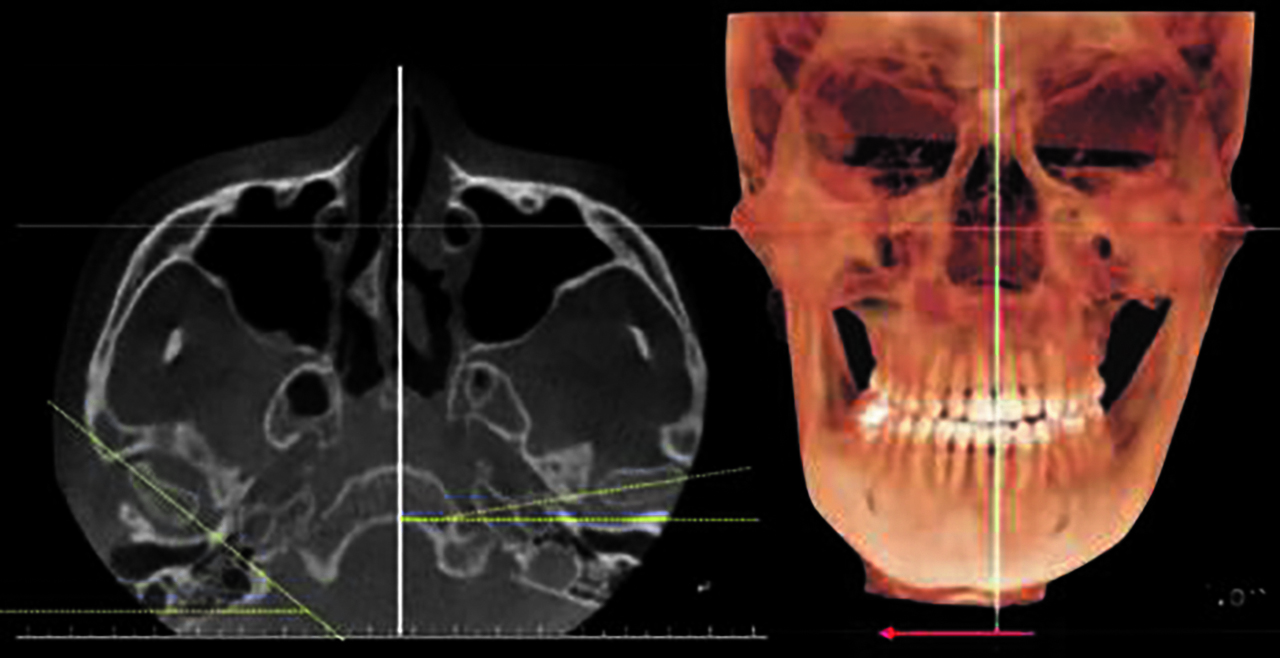

Сагиттальные параметры ВНЧС у пациентов с гнатической формой мезиальной окклюзии оценивали по величине передней, верхней, задней суставных щелей (рис. 3).

Рис. 3. Сагиттальные параметры височно-нижнечелюстного сустава.

При измерении параметров пациентов с гнатической формой мезиальной окклюзии и асимметрией нижней челюсти не было выявлено значительной разницы между величинами переднего (AS) и заднего суставного пространств (PS) [6].

Величина верхнего суставного пространства (SS) у пациентов с гнатической формой мезиальной окклюзии и асимметрией нижней челюсти несколько отличалась, а именно отмечалось более верхнее положение мыщелка на девиирующей стороне (Dv) по сравнению с недивирующей стороной (NDv) (p < 0,01) и по сравнению с аналогичным параметром (SS) у пациентов с симметрией нижней челюсти (p < 0,05) (табл. 1).

Как следует из табл. 2, лишь величина SS у пациентов с гнатической формой мезиальной окклюзии и асимметрией нижней челюсти демонстрирует статистически значимое верхнее положение мыщелка по сравнению с пациентами с симметрией нижней челюсти (рис. 4).